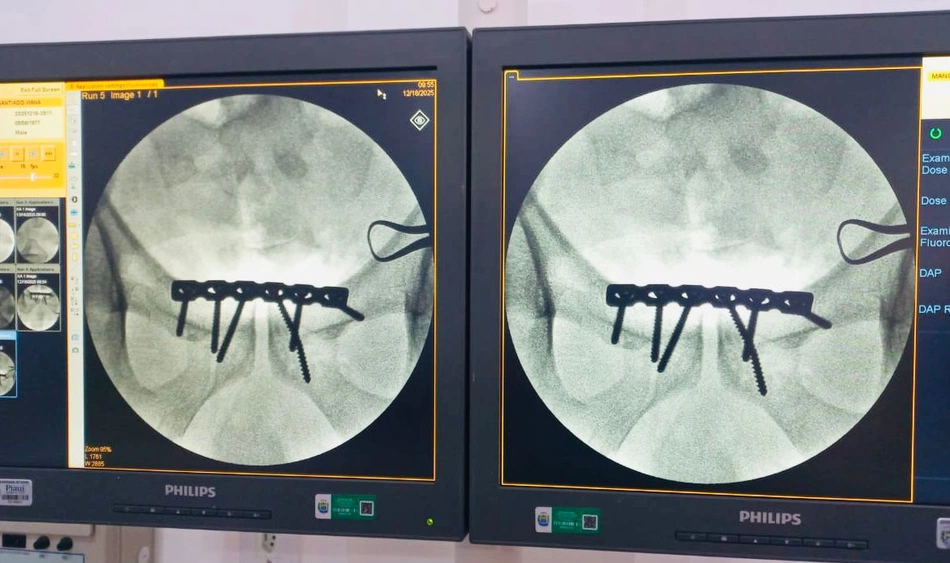

O Hospital Regional Chagas Rodrigues (HRCR), em Piripiri, realizou pela primeira vez um tratamento cirúrgico de fratura do anel pélvico, conhecida popularmente como fratura da bacia. O procedimento representa um marco histórico para a unidade e sinaliza um avanço importante na ampliação dos serviços ortopédicos de média e alta complexidade oferecidos à população da região.

De acordo com o governo, a fratura do anel pélvico acontece nos ossos do quadril, sacro e cóccix e, nos casos mais graves, envolve ruptura do anel em mais de um ponto, o que torna o tratamento mais complexo e exige intervenção especializada.

Segundo o governo, o paciente atendido, um homem vítima de trauma automobilístico, apresentou fratura do tipo “livro aberto”, considerada grave. Até então, ocorrências desse porte demandavam transferência para hospitais de referência em Teresina.

A cirurgia foi realizada no próprio HRCR por uma equipe multiprofissional especializada, formada pelo cirurgião Gutemberg Soares, com auxílio do Dr. Felipe Verner, anestesia conduzida por Erick Zenteno e suporte fundamental da equipe de enfermagem. Todo o procedimento contou com estrutura adequada, materiais específicos e segurança assistencial, comprovando a capacidade técnica da unidade para atender casos de maior complexidade.